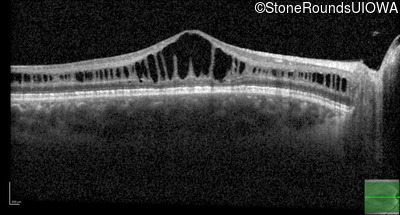

Optical Coherence Tomography - Right - 20/63 -2

Exemplar / OCT Stack